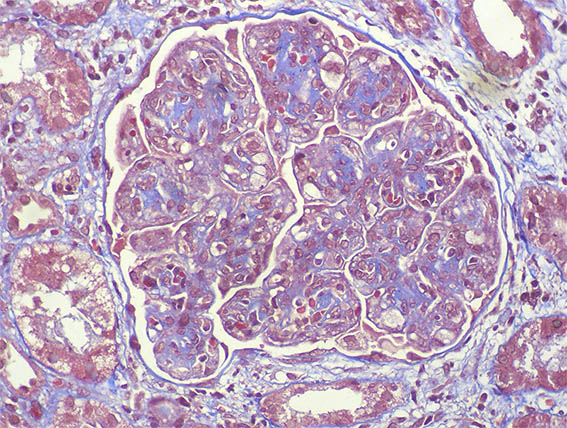

A renal biopsy was done, see the images.

Figure 5. Masson's trichrome stain, X400.